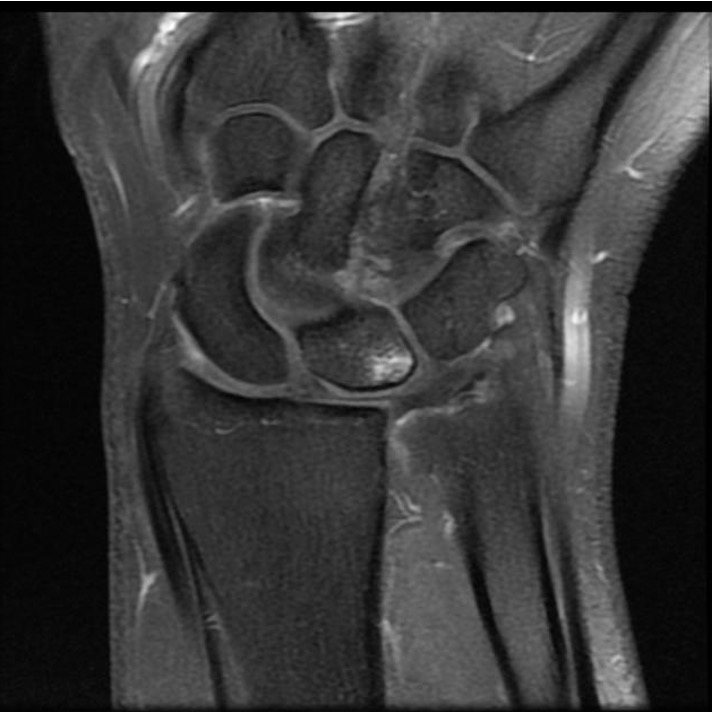

MRI

Normal

TFCC tears

Ulno-carpal abutment

Ulnocarpal abutment and lunate chondromalacia

Ulna positive with ulnocarpal osteoarthritis

Class 2 Degenerative TFCC tears

Central TFCC tear with ulna positive variance an ulnocarpal abutment on MRI